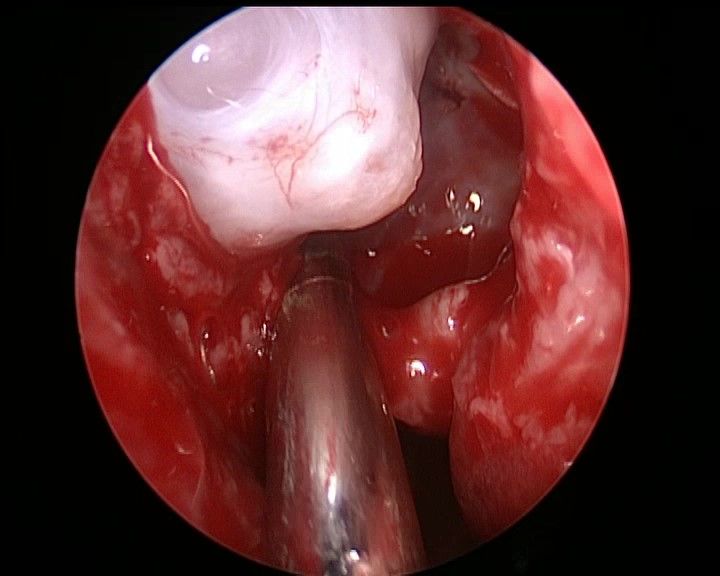

去除钩突、开放筛窦,观察筛房 ↓

↑ 去除筛泡、清理筛窦气房后观察右侧眶纸板